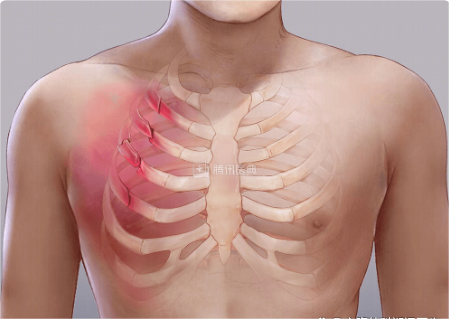

二、发生胸部外伤时怎么办?

1

当外伤程度较轻,胸部疼痛感不是很严重时,可选择观察几日,后续疼痛感觉越来越轻则发生骨折的概率较小,建议继续观察;

2

当观察几天后感觉疼痛越来越剧烈,深呼吸、咳嗽和打喷嚏时疼痛会加剧,这时候就需要及时就医;

3

如果老年人发生胸部外伤时,建议及时就医,因为老年人对疼痛的感觉比较迟钝,加之骨骼脆性较大,更容易发生肋骨骨折。